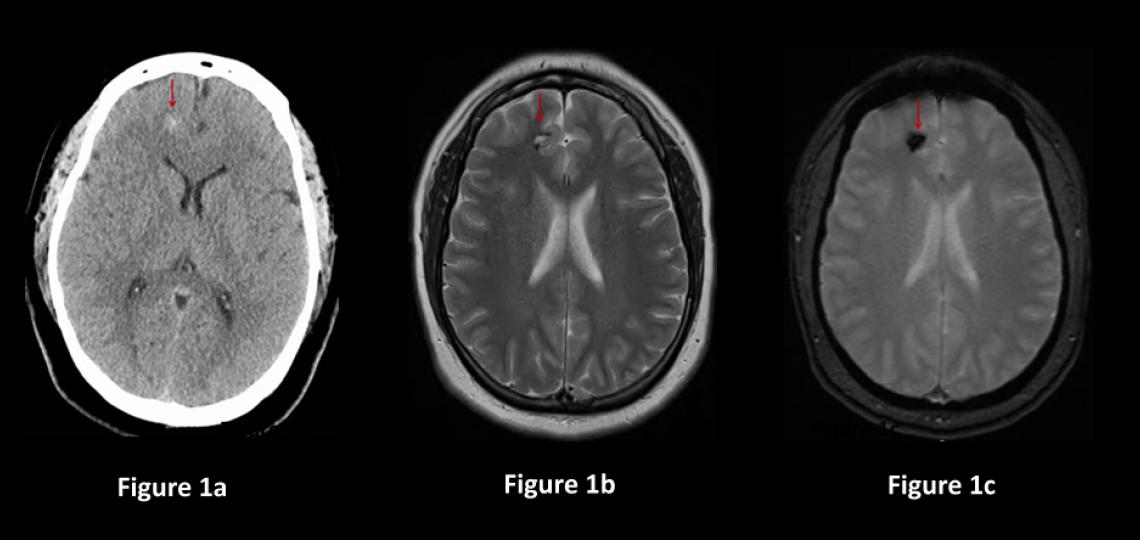

Direct removal of the cavernous malformation with surgery is the only known cure. Surgery is often recommended for cavernous malformations that are causing symptoms, grow on repeat imaging, bleed and are easily accessible by traditional neurosurgical methods with low risk of harming the surrounding brain (Figure2). The decision to treat cavernous malformations is nuanced and should be discussed between the patient and their cerebrovascular neurosurgeon.

Figure 2a: Brain CT scan in a patient having difficulty speaking shows a 3cm mass containing blood (red arrow). Figure 2b: Brain MRI showing the mass with blood inside (red arrow). Figure 2c: CT scan of the brain after surgery showing the cavernous malformation removed (red arrow) and less brain shift.